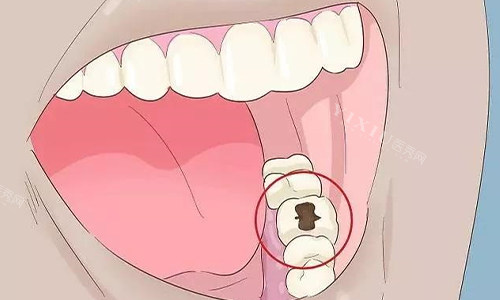

补牙项目

国产普通树脂补牙(前牙):158 元起

国产普通树脂补牙(后牙):208 元起

进口树脂补牙(前牙):258 元起

进口树脂补牙(后牙):308 元起

玻璃电荷补牙(前牙):188 元起

玻璃电荷补牙(后牙):238 元起

复合树脂美学补牙(前牙):450 元起

复合树脂美学补牙(后牙):550 元起

补牙价格根据材料和牙齿位置而定,进口材料在质量和美观度上更有优势,价格也会高一些。